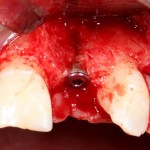

В этом случае остеопластика делается отдельной процедурой. Ее принципы точно те же, но уже без импланта. Например:

Имплантировать в таких условиях — заведомо обрекать себя на хреновый, с точки зрения эстетики и функциональности, результат. Поэтому первым этапом проводим остеопластику. Объем небольшой, использовать в таких объемах костный блок не очень рационально. Воспользуемся аутокостной стружкой и мембраной.

Сначала фиксируется BioGide. Это легко:

Затем укладывается и конфигурируется аутокостная стружка:

Если после этого BioGide намочить физраствором, им легко укрыть получившийся объем: